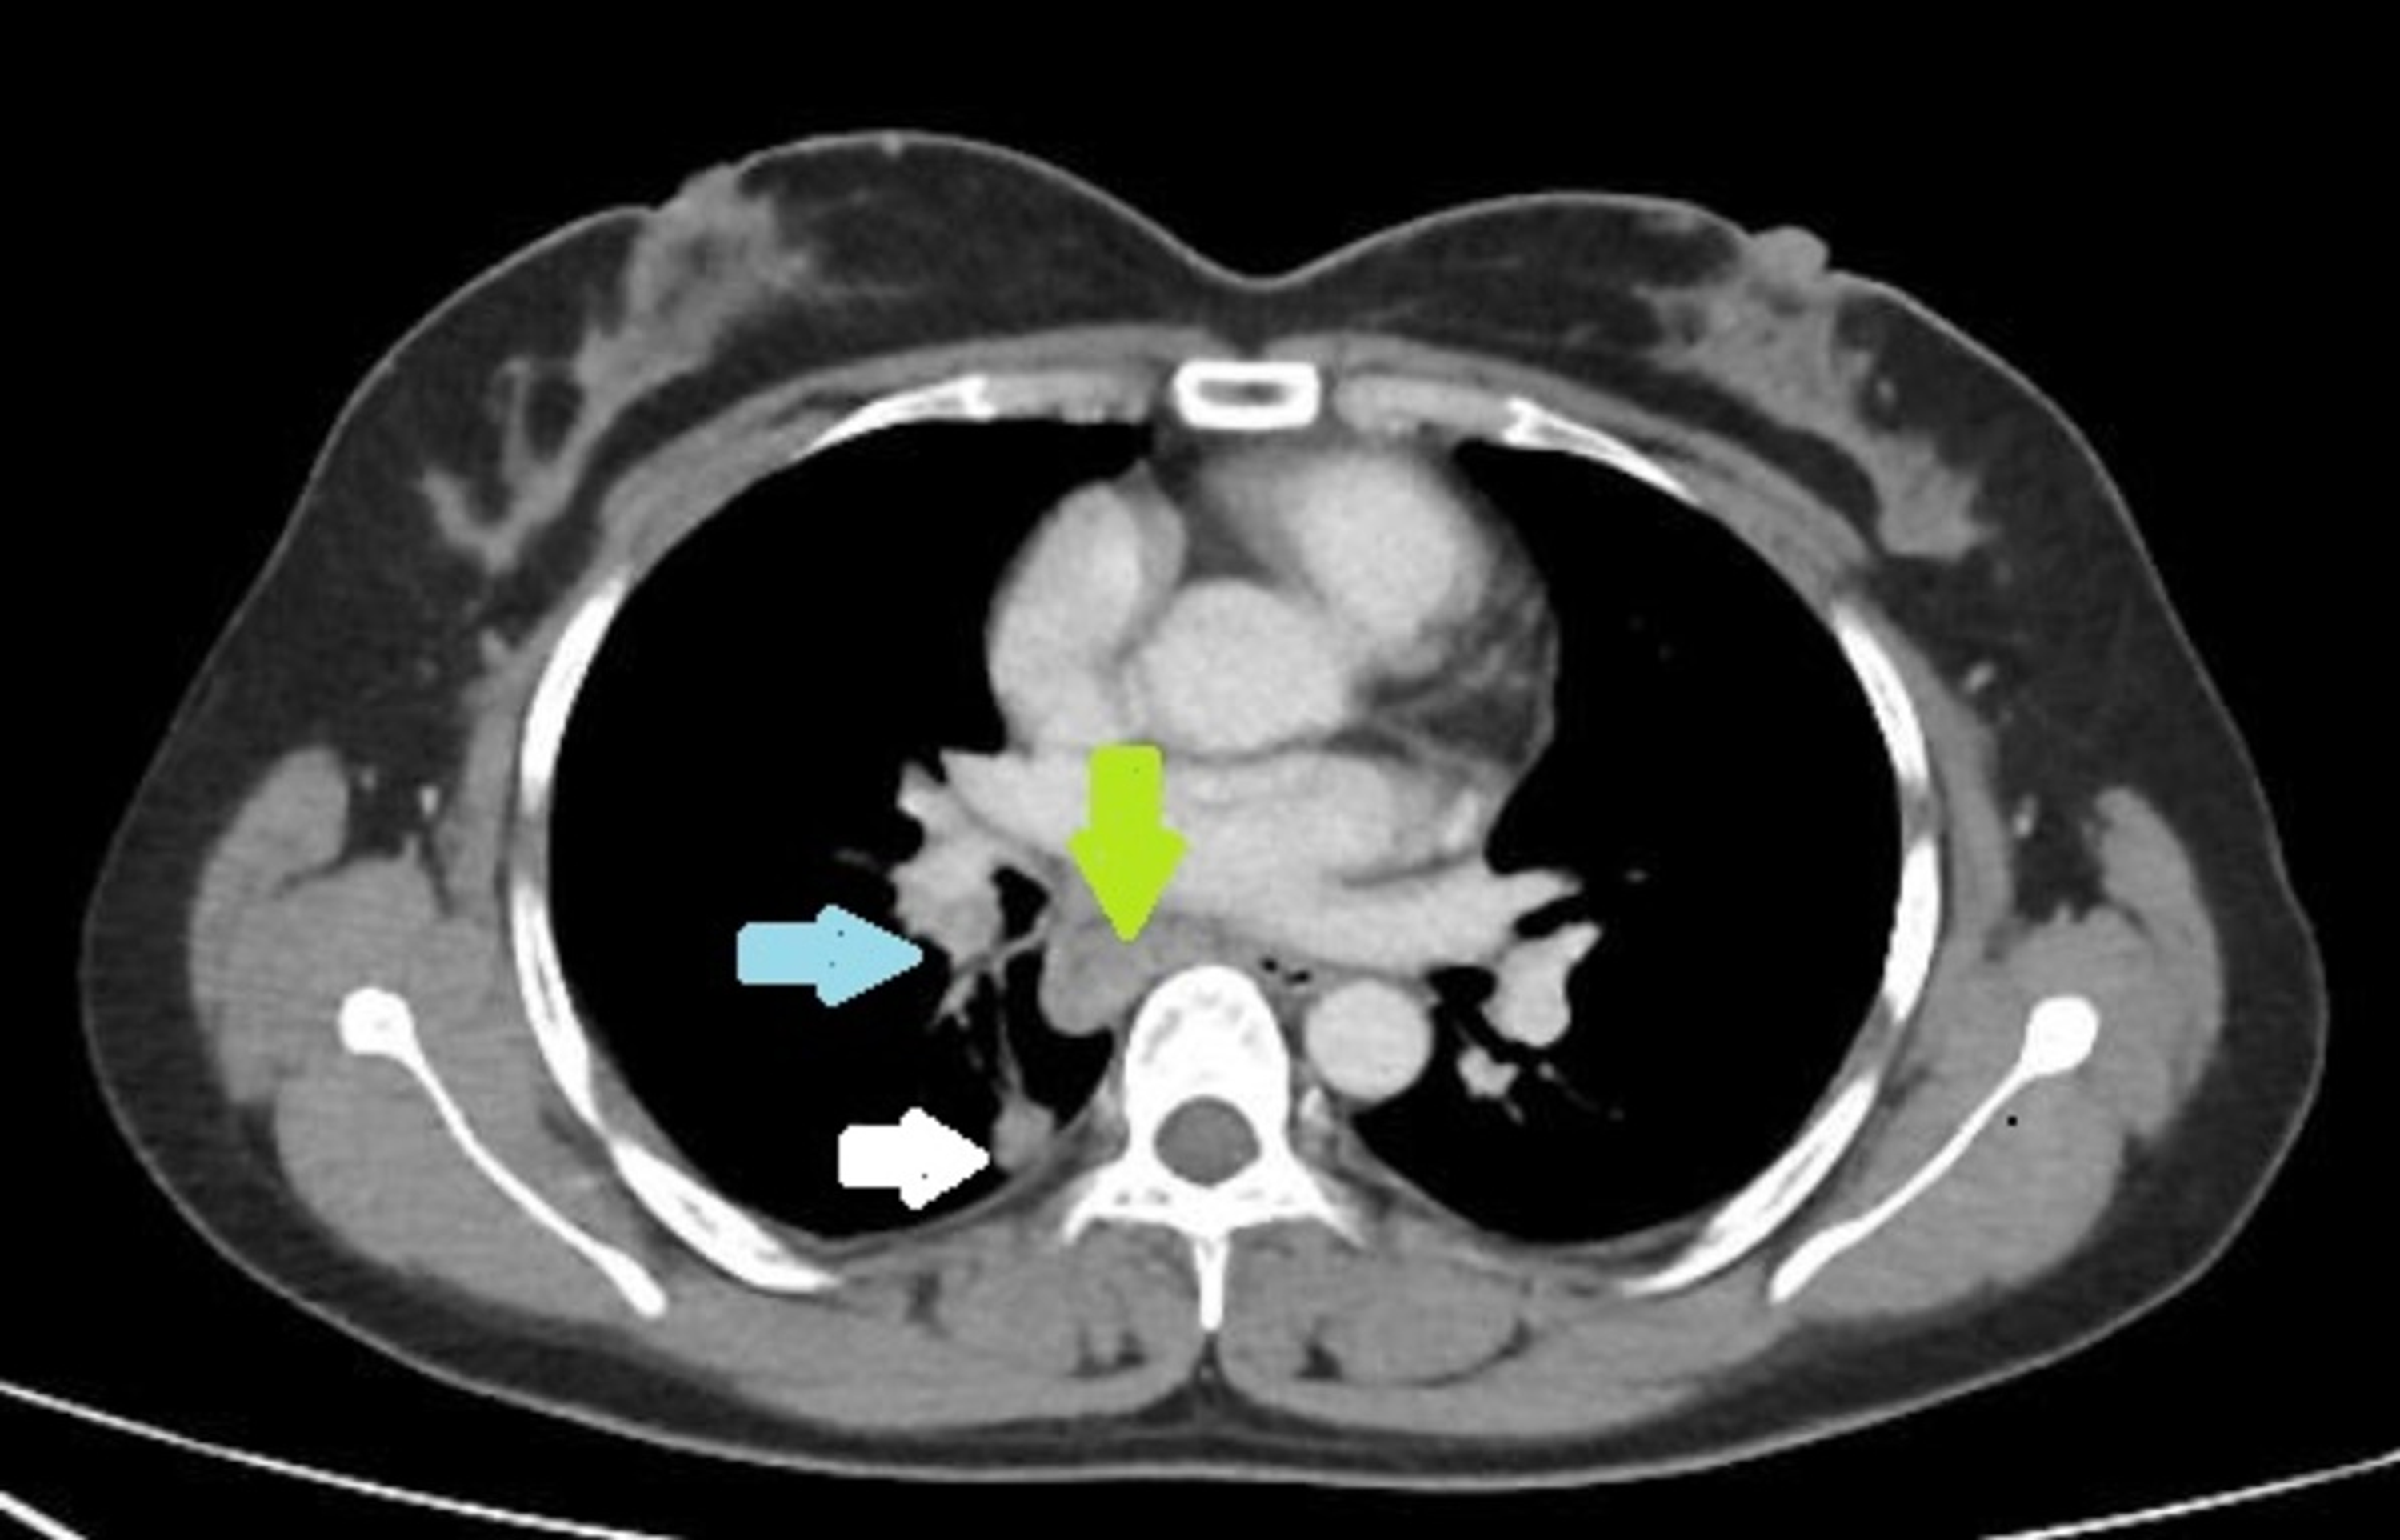

From medschool.co

Hilar Nodes / Masses Chest XRay MedSchool Spiculated Node  Less commonly, they can be caused by a more serious condition such as lung cancer. Pt scan friday for further evaluation. I have spiculated 9mm nodule in the right upper lobe of my lung. Most lung nodules are not cancerous. For example, lower lobe lung nodules often are found during a ct scan of the abdomen or pelvis. Calcified lung. Spiculated Node.